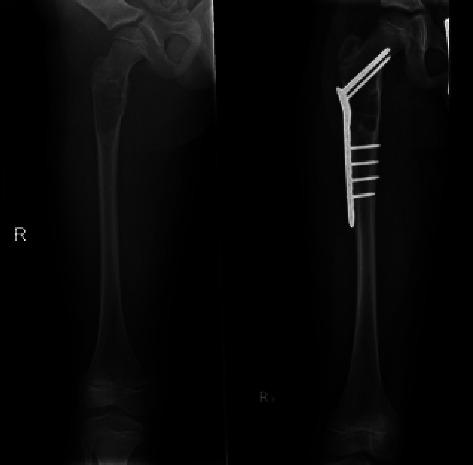

A total of 15 patients were included in our study, with a mean follow-up of 118 weeks. 86.7% of patients demonstrated clinical resolution (absence of pain at the latest follow-up) and 80% of patients demonstrated radiographic resolution. Only one patient sustained a subtrochanteric fracture post-index operation, whilst two others demonstrated redevelopment of cystic architecture on follow-up.

我们的研究共纳入15例患者,平均随访118周。86.7%的患者临床症状缓解(在最近一次随访时无疼痛),80%的患者影像学表现缓解。仅1例患者在首次手术后发生转子下骨折,另外2例患者在随访时囊肿结构复发。